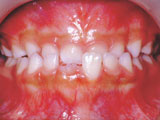

症例1:乱ぐい歯「歯並びが乱れている」

治療後